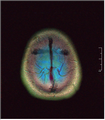

- obrazy T1-zależne (zob. ilustracja), najlepiej oddające wizualnie strukturę anatomiczną mózgu, gdzie istota biała jest ukazywana w jasnych kolorach, zaś istota szara w ciemnych, płyn mózgowo-rdzeniowy, ropień i guz na ciemno, a miąższ wątroby na jasno